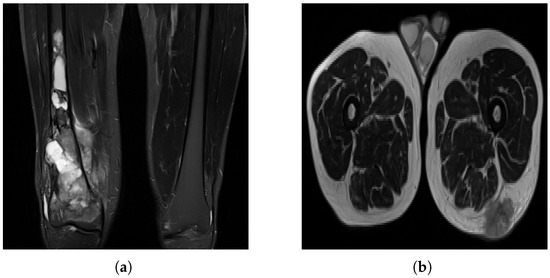

Non-pathological tissue was grouped as healthy, which can cause misclassification, as biological tissue may resemble pathological regions (Figure 4). Small homogeneous regions in segmented 3D images may confuse the model, especially when similar to healthy tissue. Image quality varied significantly between patients (Figure 5), with some images being grainy, blurred or corrupted, which may affect model performance.

Figure 4. An example of how healthy and pathological tissue can overlap in terms of appearance. The left two images show healthy tissue, and the rightmost image shows a tumor region.